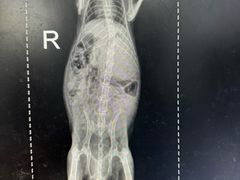

• 瑞派·关忠动物医院·异宠专科·犬猫肿瘤·皮肤专科(望京店)

• -瑞派·关忠动物医院·异宠专科·犬猫肿瘤·皮肤专科(望京店)

匿名用户 | 24-05-05